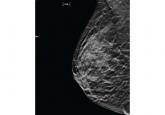

ArticleScreening mammography starting at age 40: Still relevantAuthor:Karthik Ghosh, MDPublish date: May 1, 2015In women in their 40s, the incidence of breast cancer is low but the risk of a tumor being aggressive is especially high.Read More